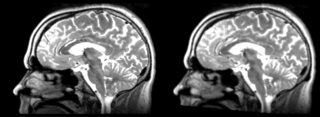

Original file(1,162 × 426 pixels, file size: 350 KB, MIME type: image/png)

Registration of a t2w image to arbitrary t1 and back via Rigid Registration module.

current15:08, 21 April 2009Thumbnail for version as of 15:08, 21 April 20091,162 × 426 (350 KB)Rauscha (talk | contribs)Registration of a t2w image to arbitrary t1 and back via Rigid Registration module.